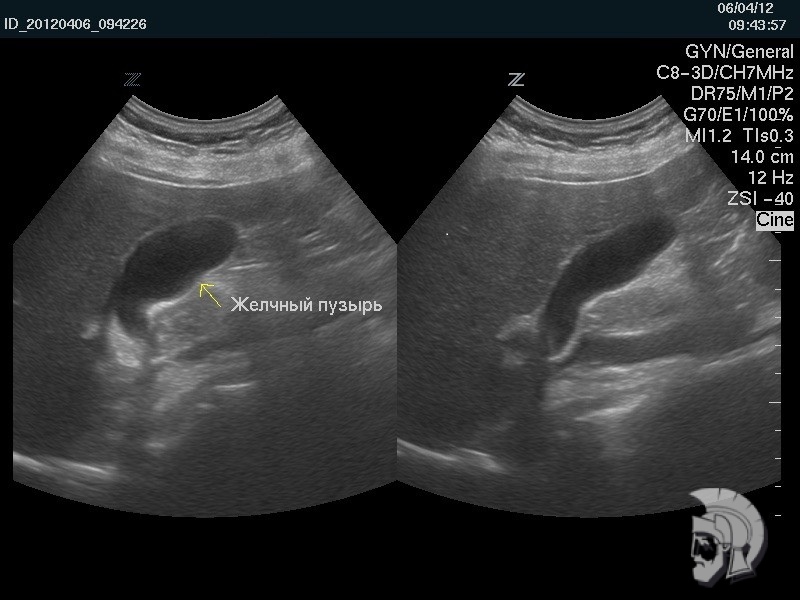

Фото желчного пузыря.

Исследование функциональной активности желчного пузыря у мужчины 35 лет: желчный пузырь правильной формы в начале исследования (слева) и после частичного опорожнения (справа) |